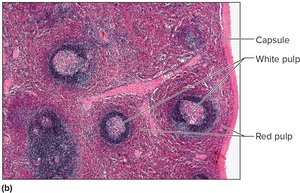

Spleen

The spleen is the largest lymphatic organ, located in the upper left abdominal cavity. It filters blood, removes damaged cells, and contains white pulp (lymphocytes) and red pulp (red blood cells, macrophages, lymphocytes).